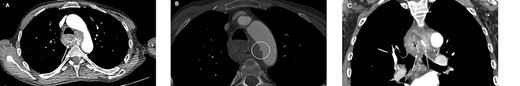

An urgent CT scan with triple-phase contrast revealed an impacted foreign body in the mid-oesophagus, with peri-oesophageal fat-stranding, forming an inflammatory mass abutting the aortic arch. There was no evidence of perforation. There was subtle evidence of aortic arch ulceration (outpouching at the medial aspect of the aortic arch directed towards the oesophagus at the level of the foreign body) suggestive of an AOF, as shown in Fig. 1. There was no extravasation of contrast to indicate active bleeding, although we suspect he had suffered an initial herald bleed.

A computerized tomography scan with contrast in the arterial phase showing the AOF and denture in the oesophagus. (A) Axial plane view with arrows pointing to denture within the oesophagus, (B) axial plane view with AOF circled and (C) coronal plane view with arrows pointing to denture within the oesophagus.